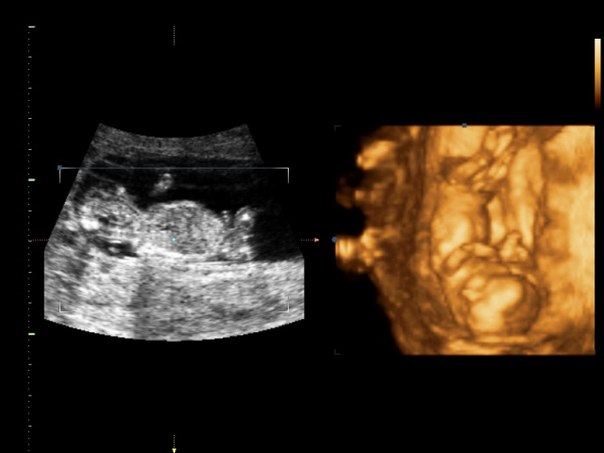

И вот уже 13 недель. Вернее они почти закончились. Решила рассказать как оно...